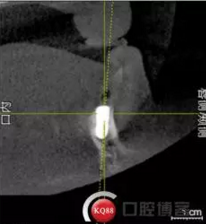

檢查:上頜無(wú)牙頜假牙穩(wěn)定性尚可,下頜3435364243殘根;33殘冠1-2度松動(dòng),其他牙齒缺失;CBCT檢查:下頜牙槽骨前牙區(qū)骨高度足,后牙區(qū)骨高度最低為8mm,骨寬度足。

2)術(shù)前準(zhǔn)備及手術(shù)過(guò)程,測(cè)量血壓及血糖,簽種植知情同意書;嚴(yán)格遵循無(wú)菌操作,局麻下采用微創(chuàng)技術(shù)于323436分別植入osstem4.0X10,4.0X10,4.5X7; 434446分別植入osstem4.0X1O,4.0X10,4.5X7.初期穩(wěn)定性均達(dá)到了35N.CM以上;嚴(yán)密縫合,止血,種植體位點(diǎn)和方向與設(shè)計(jì)一致。